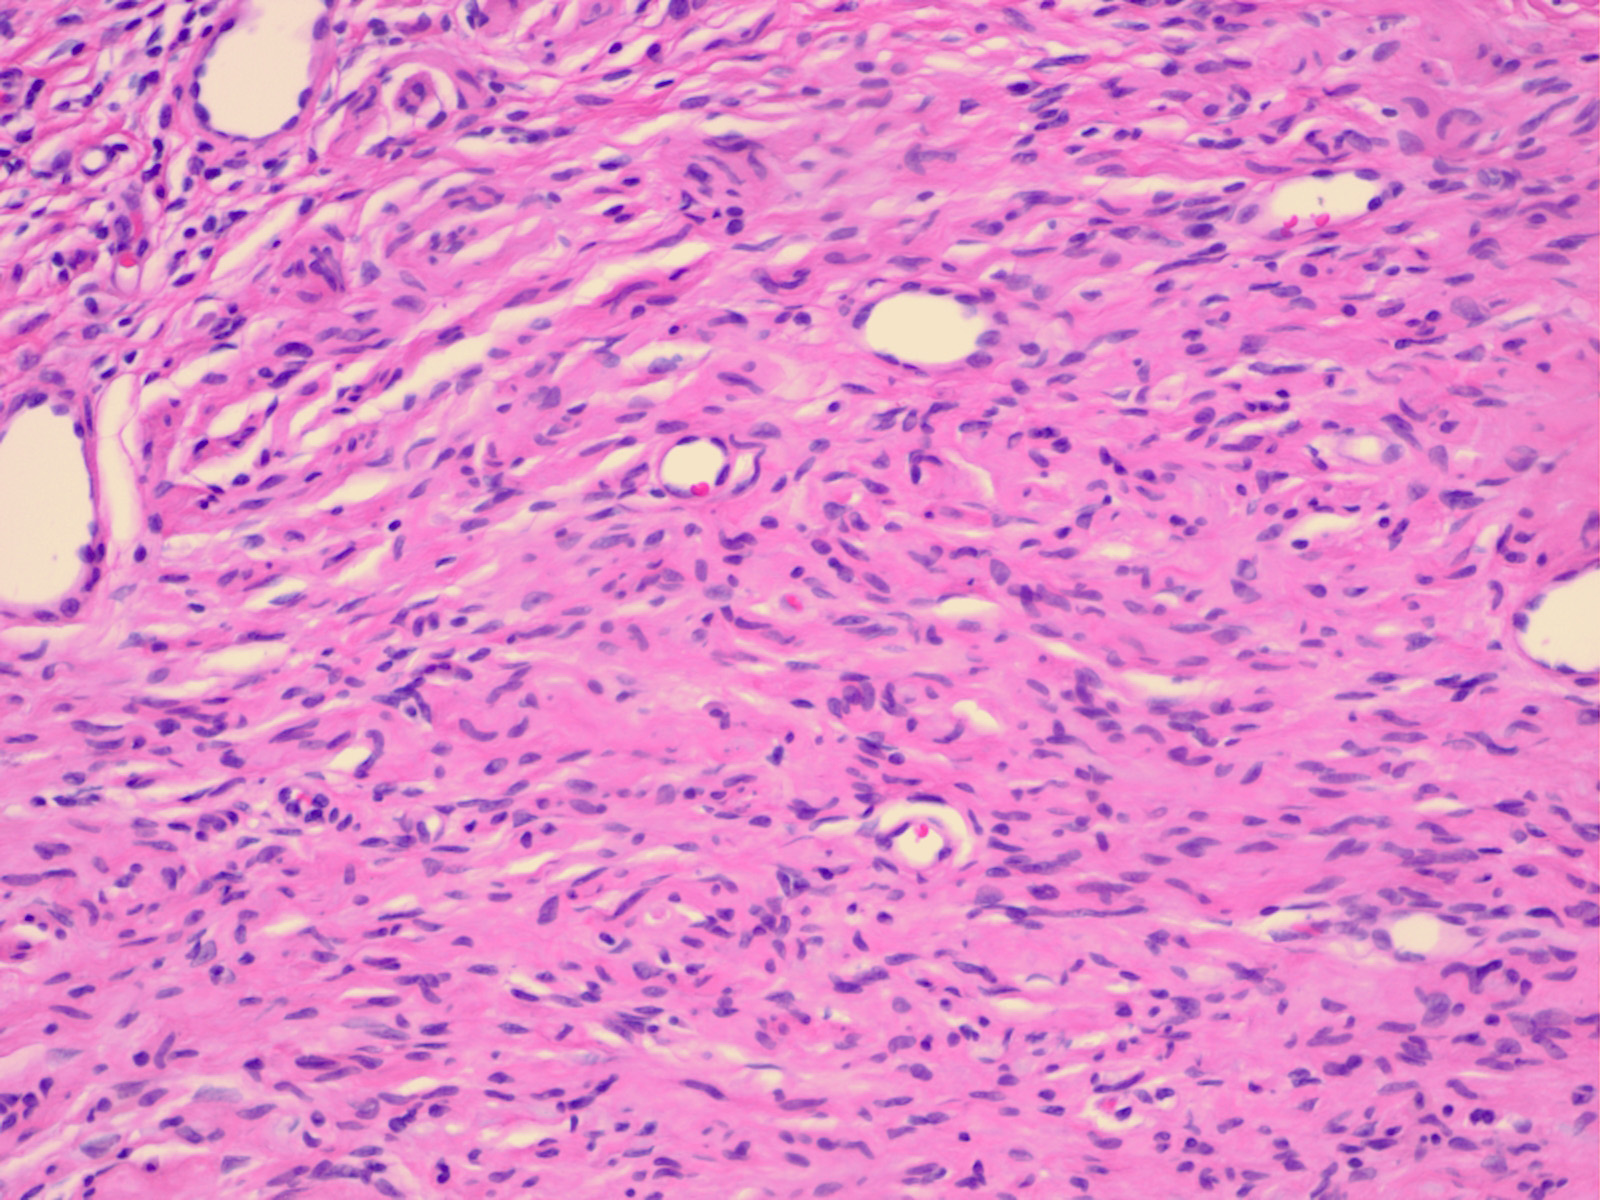

Neurofibroma = الليفوم العصبي